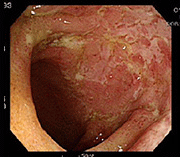

사례 2

치료 후 치료 후 장내 점막 회복 사진